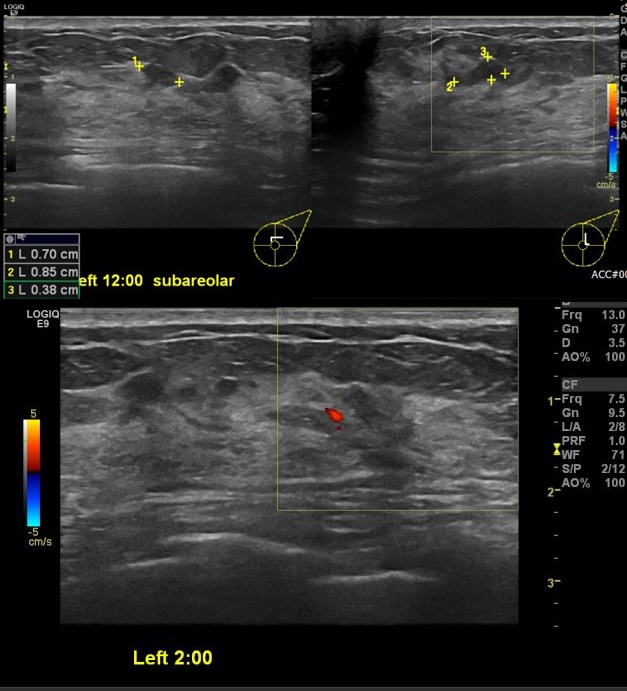

건강검진상 이상 소견으로 내원하신 40대 여성분으로 좌측 12시 방향 유두 밑, 2시 방향 의심스러운 혹 조직검사 시행하여 좌측 유관암 진단 되었습니다.